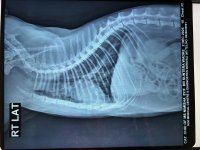

In mid Sept, she again got an x-ray with bloodwork (both attached) and got prescribed Omnacortil (Prednisolone), Bioclan (Clindamycin Hydrochloride) and Fexorise (Fexofenadine Hydrochloride IP 120 mg). She was ok for nearly 1.5 months before the wheezing returned along with a sort of cough too.

I'm attaching her labs (Mar/Jul/Sep), x-rays (Aug/Sep/Nov/Dec) and 2d-echo (Dec).

2. Xray - RT LAT - Chiu - 17Sep2025.jpeg1.5 MB · Views: 34